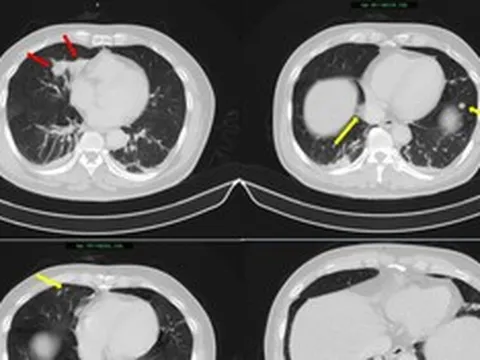

Tp.HCM mở 60 điểm khám tầm soát ung thư miễn phí cho người dân - Ảnh 1.

Ảnh minh họa.